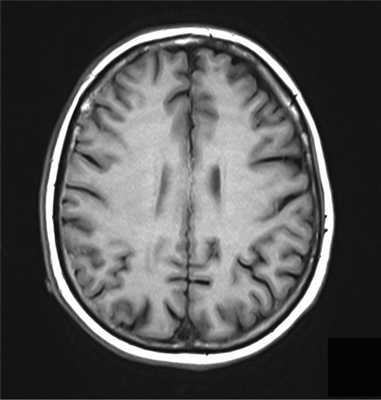

У пациентки Л. в возрасте 41 года заболевание проявило себя эпилептическими приступами, парезом правой руки (до 2 баллов), элементами моторной афазии, акалькулией (нарушением счета). Индекс Карновского — 80. На сериях магнитно-резонансной томографии (МРТ) определялось внутримозговое объемное образование в левой лобной доле с зоной перифокального отека и неоднородным гиперинтенсивным сигналом во всех режимах (признак кровоизлияния в строму опухоли) (рис. 1, а—в). Рис. 1. Первичная лимфома ЦНС левой заднелобно-теменной области. а — МР-картирование; б — МРТ в Т1-режиме с контрастным усилением; в — МРТ Т2 FLAIR; г — полная ремиссия опухоли после ИА ХТ. Впервые больная госпитализирована в ФГАУ «ННПЦН им. акад. Н.Н. Бурденко» Минздрава России в 2010 г. После костно-пластической трепанации черепа проведено удаление внутримозговой опухоли левой заднелобно-теменной области с применением интраоперационного картирования речевых и двигательных центров. Иммуногистохимическое исследование биоптата обнаружило В-клеточную лимфому c положительной экспрессией общего лейкоцитарного антигена, CD10 и CD20. Пациентке проведено 9 сеансов интраартериальной химиотерапии (ИА ХТ). После временного открытия гематоэнцефалического барьера по катетеру введено 3000 мг метотрексата, а также 300 мг карбоплатина + 1000 мг циклофосфамида. Однако при осмотре офтальмологом была выявлена двусторонняя ПИОЛ в начальной стадии. Несмотря на сохранные зрительные функции обоих глаз, пациентку в течение 2—3 лет беспокоили плавающие помутнения. При биомикроскопии с медикаментозным мидриазом в стекловидном теле на фоне его деструкции имелась взвесь белесых мелкоклеточных форменных элементов. Ультразвуковое исследование (УЗИ) продемонстрировало участки повышения Эхо-плотности в стекловидном теле (рис. 2, а, Рис. 2. В-сканы глазных яблок. а — ПИОЛ правого глаза до лечения; б — после ИВ ХТ (полный ответ); в — ПИОЛ левого глаза до лечения; г — после ИВ ХТ (полный ответ). в). Роговицы и сетчатки были интактны. В конце курса ИА ХТ была достигнута полная ремиссия лимфомы головного мозга (рис. 1, г). При участии офтальмоонколога проф. Е.Е. Гришиной больной проведены интравитреальные инъекции метотрексата (разовая доза 400 мкг/0,1 мл) через плоскую часть цилиарного тела (табл. 1, 2). Таблица 1. Результаты лечения ПИОЛ правого глаза Примечание. * — visus — острота зрения; ** — в феврале 2013 г. проведена факоэмульсификация катаракты с имплантацией интраокулярной линзы; *** — на момент написания статьи; прочерк — осложнений не наблюдалось. Таблица 2. Результаты лечения ПИОЛ левого глаза Примечание. * — visus — острота зрения; ** — на момент написания статьи. Лечению предшествовали частичная витрэктомия, аспирационная биопсия стекловидного тела левого глаза. Полимеразная цепная реакция подтвердила В-клеточную клональность по реаранжировкам генов тяжелых цепей иммуноглобулинов. В результате интравитреальной ХТ (ИВ ХТ) достигнут полный ответ на лечение (рис. 2, б, г). Безрецидивный период составил 4 мес для правого глаза и 5 мес — для левого. В связи с рецидивом ПИОЛ правого глаза (рис. 3, а) Рис. 3. В-сканы глазных яблок. а — рецидив ПИОЛ правого глаза после ИВ ХТ; б — после СРТ (частичный ответ); в — рецидив ПИОЛ левого глаза после ИВ ХТ; г — после СРТ (полный ответ). в сентябре 2012 г. проведен курс стереотаксической радиотерапии (СРТ) с применением линейного ускорителя «Novalis» с микромультилепестковым коллиматором. Лучевую терапию проводили на область правого глазного яблока с разовой дозой облучения (РДО) =1,8 Гр до суммарной очаговой дозы (СОД) 36 Гр при 5-дневном облучении в неделю. СРТ проводили с трех динамических арок с одним изоцентром, энергия излучения составляла 6 МэВ, объем мишени GTV=CTV=7,516 см 3 включен в 80% изодозную кривую (рис. 4, табл. Рис. 4. План облучения ПИОЛ правого глаза с применением линейного ускорителя «Novalis», схема изодозного распределения полей с защитой хрусталика. 1). Эффект лечения — уменьшение инфильтрации стекловидного тела и стабилизация процесса (рис. 3, б). На фоне ИВ ХТ метотрексатом сформировалась осложненная заднекапсулярная катаракта правого глаза, и в феврале 2013 г. выполнена факоэмульсификация катаракты с имплантацией интраокулярной линзы. В марте 2013 г. в связи с рецидивом ПИОЛ после ИВ ХТ (рис. 3, в) проведена СРТ на область левого глаза с использованием линейного ускорителя «Novalis» с микромультилепестковым коллиматором. Энергия излучения составляла 6 МэВ: объем мишени GTV=CTV=8,649 см 3 включен в 80% изодозную кривую. Облучение проводили методом интесивно модулированной радиотерапии c 6 полей с одним изоцентром. Подведено 20 фракций по 2 Гр до СОД 40 Гр (табл. 2). В результате получен полный ответ на лечение (рис. 3, г). В феврале 2014 г. у пациентки развился рецидив лимфомы головного мозга на отдалении от первичного очага поражения. На серии МРТ выявлялось накопление контрастного вещества в области левого таламуса, в правой теменной области, в правой гемисфере мозжечка. Это состояние сопровождалось рецидивом ПИОЛ правого глаза в виде появления белесых преципитатов на эндотелии роговицы и усилением лимфоидной инфильтрации стекловидного тела. После 8 сеансов ИА ХТ (схема и дозы химиопрепаратов приведены выше) проведен курс СРТ на область всего головного мозга и правого глазного яблока (единой мишенью). Лечение осуществляли с помощью линейного ускорителя «Primus» по системе планирования «Амфора». Объем мишени PTV составлял 1328,8 см 3 . Облучение проводили методом статических пучков (n=2), за 20 фракций подведено РДО 1,8 Гр до СОД 36 Гр. Критические структуры были в пределах толерантности (рис. 5). Рис. 5. План облучения с использованием линейного ускорителя Primus. В мишень включены весь головной мозг и зона правого глазного яблока; изодозное распределение, ориентация полей. В результате комбинированной терапии отмечались полный регресс множественных очагов лимфомы головного мозга и полный ответ со стороны ПИОЛ правого глаза после очередного курса СРТ. cведения о дальнейшем проведении третьего курса СРТ по поводу рецидива ПИОЛ правого глаза и второго курса СРТ по поводу рецидива интраокулярной лимфомы левого глаза приведены в табл. 1 и 2. Признаков рецидива лимфомы головного мозга в эти периоды не было. Безрецидивный период к моменту написания статьи для левого глаза составил 12 мес, для правого — 1 мес. Следует отметить, что во время планирования облучения анализировались дозы облучения, которые будут подведены к критическим структурам обоих глаз (табл. 3, 4). Таблица 4. Дозовые нагрузки на критические структуры левого глаза в процессе лучевой терапии ПИОЛ (в Гр) Таблица 3. Дозовые нагрузки на критические структуры правого глаза в процессе лучевой терапии ПИОЛ (в Гр)